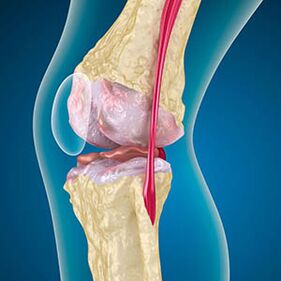

Nel caso dell'osteoartrite, la cartilagine che riveste i bordi delle ossa è un'abrasione o mancante. Il tessuto danneggiato non è una fonte di dolore perché non ha recettori. L'infiammazione nelle strutture vicine provoca sintomi caratteristici.

Il corpo continua la rigenerazione dei tessuti danneggiati, ma la cartilagine cresce in modo non uniforme. Di conseguenza, si formano irregolarità che violano altri elementi dell'articolazione. Il tipo di osteofita viene dichiarata cartilagine articolare liscia mediante compensazione. Un'altra versione mostra che la crescita di "Spurs"È associato al tentativo di stabilizzare l'articolazione nei media o lateralmente a causa dell'indebolimento muscolare.